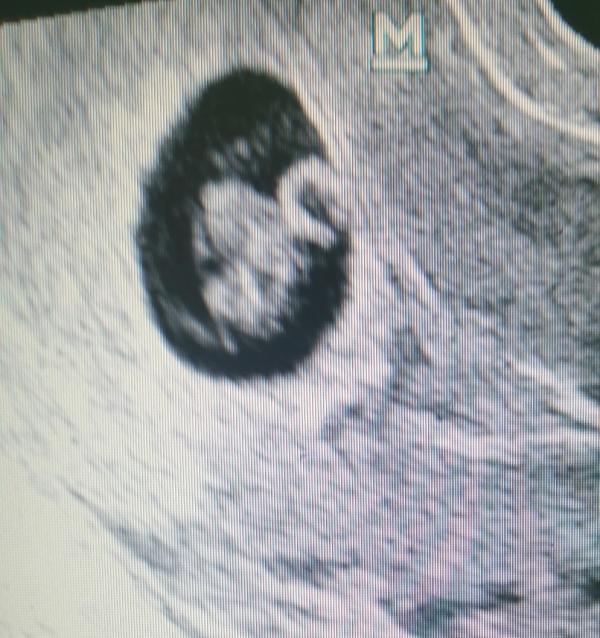

Всем привет. Была сегодня на УЗИ 🤗

Заключение: Беременность 7 недель и 3 дня. Ретрохориальная гематома (отслойка)